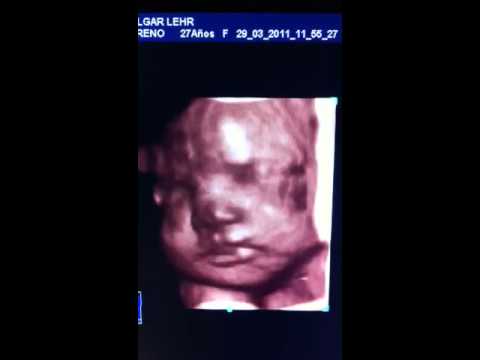

El recién nacido macrosómico es aquel cuyo peso al nacer es de 4 000 g o más. Tiene como características más relevantes el aumento de peso y de la grasa corporal y la longitud del cuerpo y la circunferencia cefálica, dan sensación de gran potencia, mayormente presentan coloración pletórica y parecen hinchados.1